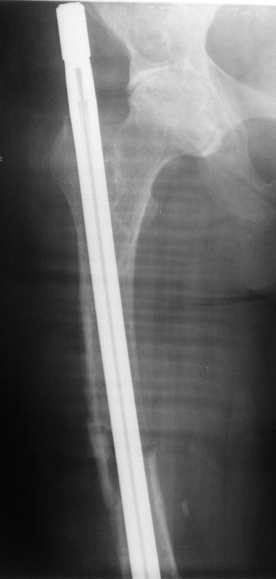

По просьбе коллег выношу на обсужение следущий случай лечения перелома бедра,

о дальнейшем лечении больной 48 лет с РПА. Анамнез: В 2005 году в ЦРБ - остеосинтез перелома

бедра пластиной. В 2007 г. воспаление в ср. трети бедра и удаление пластины. Через 2 мес. -

рефрактура и фиксация гвоздем "фикшн". Через 2 мес. после синтеза - свищ, "функционирующий"

по настоящее время. Что делать? Если бы вопрос задавался лично мне, то я бы предложил удаление

существующего фиксатора, санацию костномозгового канала, установку спейсера на тонком

сплошном титановом гвозде с последущей заменой на полноценный сплошной титановый гвоздь.

Правда, что делать с отверстием в колено, вернее как провести санацию так чтобы

минимизировать риск распространения инфекции в коленный сустав, представляется не очень